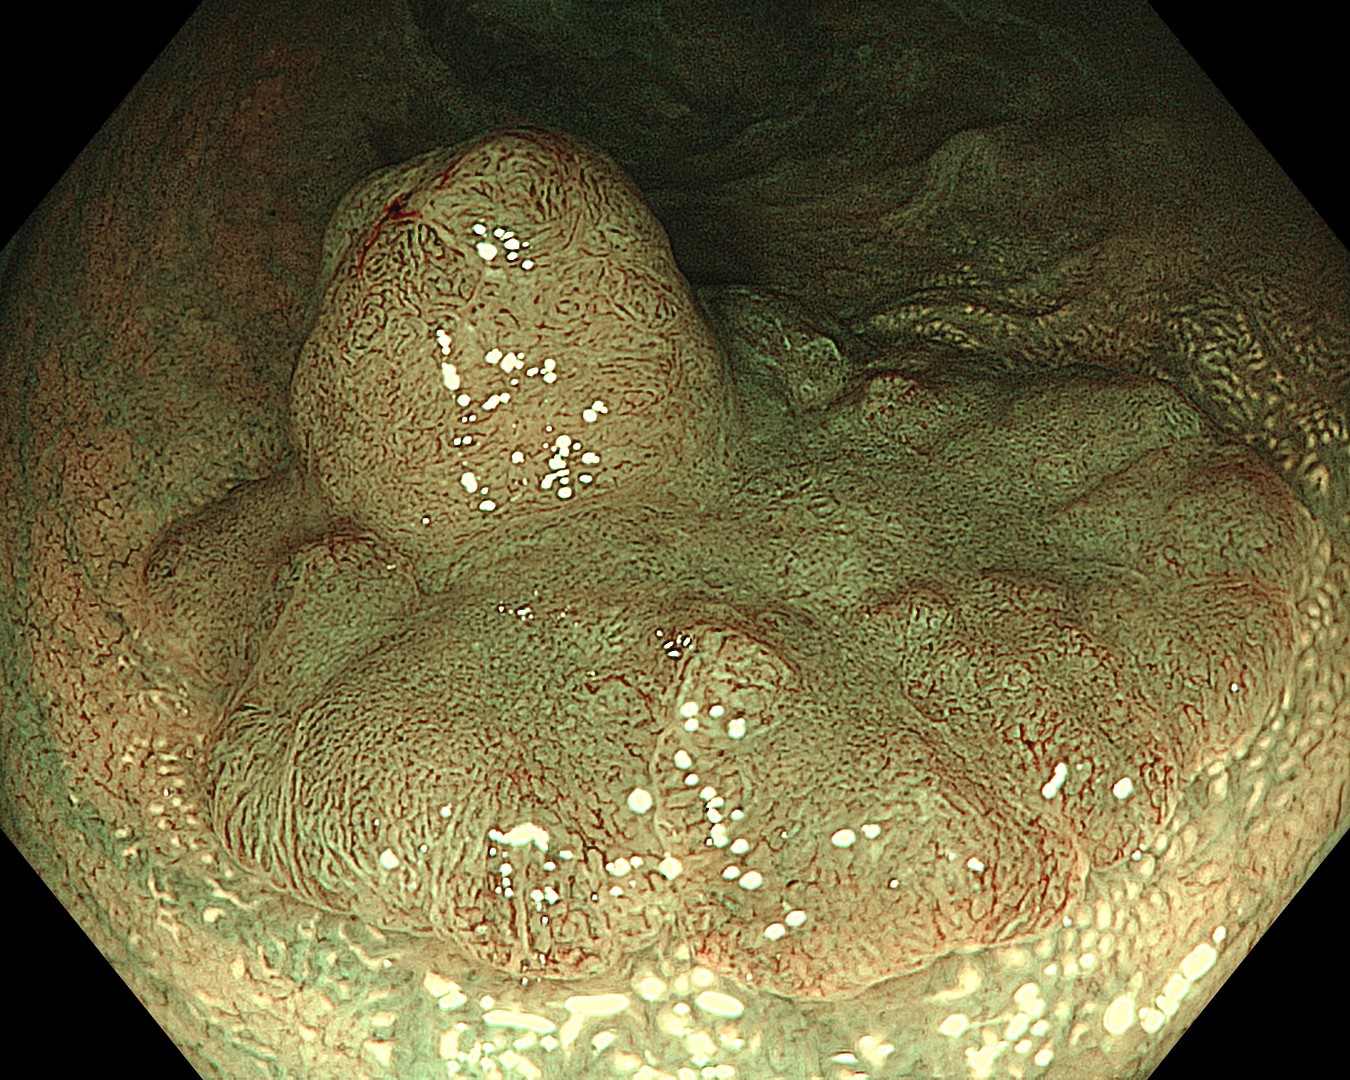

• NBI観察①(中遠景)

強調設定:A8

図3

BAI-MACにより、視野は十分に明るく、病変の全体像を鮮明に確認できた。またEDOFにより、周囲粘膜から平坦部、隆起部までの広範囲に焦点の合った画像が描出された。隆起の頂部には表面構造や血管走行の不整な領域が見られた。